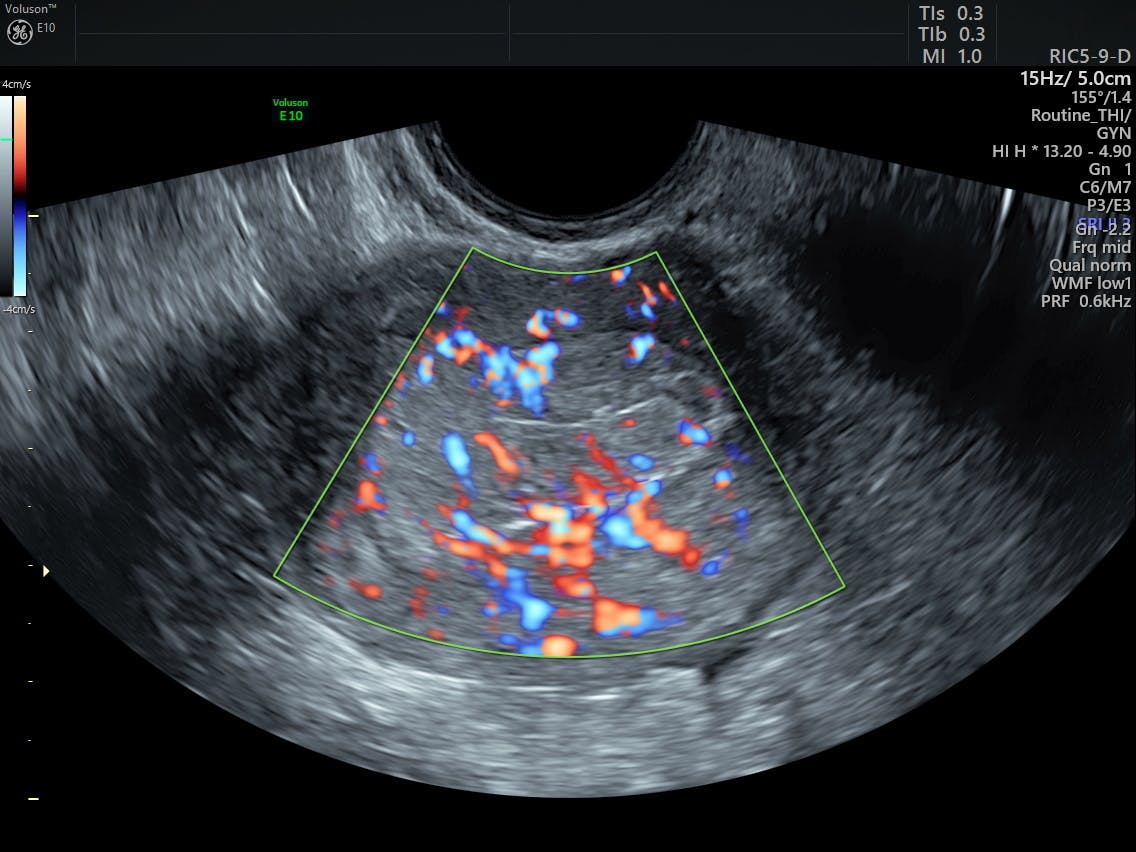

Is Uterine Cancer Common Before Menopause - Uterine cancer before menopause - eng2ro.ro - Endometrial ... : Researchers look at post menopause as key factor in endometrial cancer jan.. In endometrial cancer, cancerous cells grow in the endometrium and if it isn't caught in time or if it is left untreated, there are high chances of. Heavier than usual periods or a change in your periods. The disease generally strikes women between the ages of 50 and 65. And most of the time, the cancer is found in its earliest stage, before it has spread outside the uterus. Endometrial cancer is the most common type of uterine cancer.

How to Recognize Uterine Cancer Symptoms: 11 Steps (with ... from www.wikihow.com What are some symptoms of uterine cancer? The average age of women diagnosed with endometrial cancer is 60. The most common type starts in the endometrium, the lining of the uterus. Endometrial cancer and uterine sarcoma. Abnormal menstrual cycles or extremely long, heavy, or frequent episodes of bleeding in women before menopause may also be a sign of endometrial cancer. And most of the time, the cancer is found in its earliest stage, before it has spread outside the uterus. Uterine polyps most commonly occur in women who are going through, or have completed, menopause, although younger women can get them, too. Endometrial cancer usually occurs in women older than 50.

During natural menopause, the body's estrogen and progesterone hormone production decreases. The most common type starts in the endometrium, the lining of the uterus. Researchers look at post menopause as key factor in endometrial cancer jan. In endometrial cancer, cancerous cells grow in the endometrium and if it isn't caught in time or if it is left untreated, there are high chances of. In the united states, endometrial cancer is the most common cancer affecting a woman's reproductive system. What are some symptoms of uterine cancer? Only 10% of ec occurs before menopause. Abnormal menstrual cycles or extremely long, heavy, or frequent episodes of bleeding in women before menopause may also be a sign of endometrial cancer. That's probably because she's been exposed to more estrogen. Endometrial cancer endometrial cancer, the main type of uterine cancer, starts in the cells that make up the endometrium —the lining of the uterus. Although the exact causes of uterine cancers are not known, risk factors include women with endometrial overgrowth (hyperplasia), obesity, women who have never had children, menses beginning before age 12, menopause after age 55, estrogen therapy, taking tamoxifen, radiation to the pelvis, family history of uterine cancer, and lynch syndrome (most commonly seen as a form of inherited colorectal cancer). Endometrial hyperplasia thickens the uterus lining, causing heavy or abnormal bleeding. The good news is that it is usually cured when it is found early.

Uterine cancer is the most common cancer of the female reproductive tract. Abnormal vaginal bleeding is the most common symptom of uterine cancer. It is the fourth most common cancer and the eighth most common cause of. Endometrial cancer endometrial cancer, the main type of uterine cancer, starts in the cells that make up the endometrium —the lining of the uterus. Menopause occurs when a woman's ovaries stop releasing eggs.

A uterine fibroid is a common, benign (not cancerous) tumor that occurs on the smooth muscle of the wall of the uterus. This causes irregular menstrual periods that eventually stop. Abnormal menstrual cycles or extremely long, heavy, or frequent episodes of bleeding in women before menopause may also be a sign of endometrial cancer. Report / delete 1 reply. Uterine cancer usually happens after menopause. In the united states, endometrial cancer is the most common cancer affecting a woman's reproductive system. Atypical endometrial hyperplasia raises the risk of endometrial cancer and uterine cancer. Uterine cancer usually occurs after menopause, typically between the ages of 60 and 70. Abnormal vaginal bleeding is the most common symptom of uterine cancer. Cancers that develop in the uterus are types of sarcomas. Endometrial cancer usually occurs in women older than 50. However, it may often start earlier or later. So the more menstrual periods a woman has, the longer these tissues are exposed to estrogen.

Endometrial cancer Bleeding pattern from lh6.googleusercontent.com Cancers that develop in the uterus are types of sarcomas. Typically, menopause starts around age 50. Abnormal uterine bleeding (aub) is the most common symptom of endometrial cancer (ec) and endometrial hyperplasia with (ah) or without (eh) atypia. This type is also called endometrial cancer. The uterus, or womb, is the place where a baby grows when a women is pregnant. Mayo clinic researchers look at post menopause as key factor in endometrial cancer dec. Women at risk for cancer may choose to get a hysterectomy. In fact, abnormal bleeding happens in 90% of endometrial cancer cases.if you're postmenopausal and all of a sudden you.

There are two main types: Uterine cancer occurs when cancer cells form in the muscles of the uterus or tissues that support the uterus. Heavier than usual periods or a change in your periods. Endometrial hyperplasia thickens the uterus lining, causing heavy or abnormal bleeding. 1 uterine cancer is not common among women who have not yet experienced menopause. In endometrial cancer, cancerous cells grow in the endometrium and if it isn't caught in time or if it is left untreated, there are high chances of. One of the benefits of menopause is that it may help you catch uterine cancer early. Symptoms other than bleeding are not common. It mostly affects women after menopause. Abnormal vaginal bleeding or discharge, which occurs in nine out of 10 women with endometrial cancer. Endometrial cancer is the most common type of uterine cancer. Typically, menopause starts around age 50. During natural menopause, the body's estrogen and progesterone hormone production decreases.